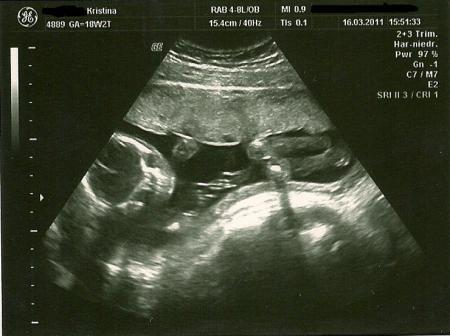

die volle Dröhnung haha Naja ich hab sehr starke probleme mit meinem Ruecken und dann immer diese ziehen da unten wen ich mal draussen zu viel gelaufen bin ! aber so langsam laesst das alles nach und jeztzt kommt das mit Nachts nicht mehr einschlafen koennen Naja hab zurzeit viele Probleme von zuhause auszuziehen! klappt nich so wie ich es gerne haette ! und ich wollte es noch vor der Geburt eig hinkriegen :( Klaaa trotz alle dem freue ich mich riesig auf den kleinen Mann Hier mal ein Foto von meinem Kruemmel wie er schoen eingekuschelt dadrin liegt

Bild zu